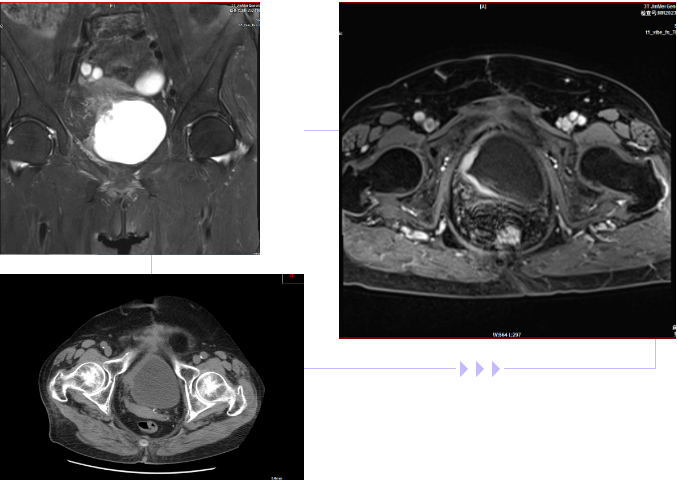

李奶奶(化名)今年73歲高齡,因?yàn)槟蝾l、尿急、間斷發(fā)熱等身體不適,就診于泌尿外科。據(jù)了解,李奶奶曾因膀胱惡性腫瘤,進(jìn)行了“膀胱部分切除術(shù)”。通過(guò)對(duì)認(rèn)真詢問(wèn)病史和詳細(xì)的體格檢查,結(jié)合腹部CT、磁共振等檢查,明確診斷為“膀胱惡性腫瘤術(shù)后復(fù)發(fā)”。